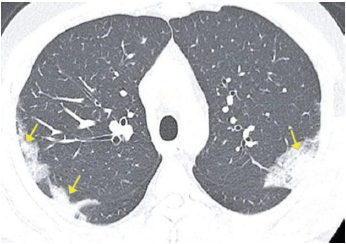

Paciente masculino, de 41 anos, apresentando tosse, febre e dispneia há 5 dias, realizou a seguinte tomografia computadorizada e aguarda resultado do PCR de swab nasal. Sobre a possibilidade diagnóstica de COVID-19, é correto afirmar que